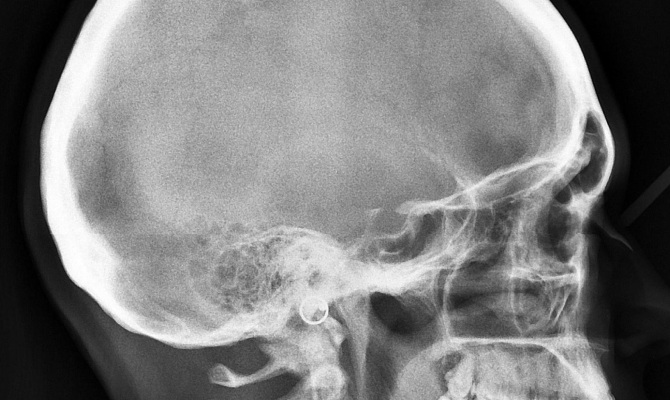

Рентген головного мозга

В верхнечелюстных пазухах с двух сторон, визуализируются затемнение полуовальной формы, имеют четкие, ровные контуры. Данные изменения больше выражены справа